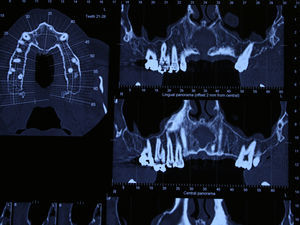

Case reportA case of a nasopalatine duct cyst in a 45-year-old male is presented (Fig. 1). The patient was referred, reporting a pressure over the anterior maxilla. There were no other symptoms and no recent history of pain. Clinical examination revealed a palatal expansion on the anterior hard palate (Fig. 2). There was no previous history of trauma. The patient was asked to take a computerized axial tomography which showed a well-defined radiolucency in the anterior maxilla in the region of incisive canal (Fig. 3). Loss of cortical bone was seen along the palatal aspect of the lesion in the sagittal sections (Fig. 4). Also resorption of nasal cavity floor bone could be seen in those sections. The cyst was enucleated under general anaesthesia. A palatal mucoperiosteal flap was raised and following bone removal, the friable, haemorrhagic cyst lining was curetted and sent for histological examination fixed in 10% neutral formalin (Figs. 5 and 6). After cyst removal it could be seen in the depth of surgical loca a small communication with the nasal cavity. Gross examination revealed a whitish, soft consistency fragment measuring 2.2cm×1.5cm×0.4cm (Fig. 7). Microscopic examination revealed fibrous wall lined by thin stratified squamous epithelium without inflammatory infiltrate and with some clear cells of ciliated appearance, which confirms the diagnosis of nasopalatine duct cyst (Fig. 8). The patient showed no clinical or radiographic signs of recurrence one year after surgical excision (Fig. 9).